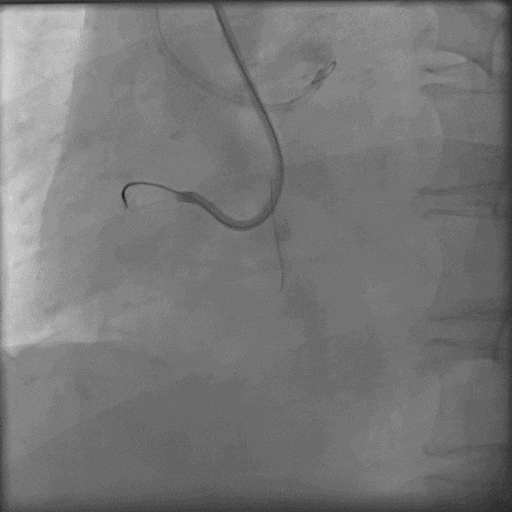

换用P200,导丝幸运进入血管真腔,

导丝通过后,Corsair微导管耐心旋转无法通过,小球囊无法通过;

采用M12、CP8-20导丝挤压(未留影),再小球囊掘进联合BAM技术;

Corsair微导管耐心旋转通过病变;